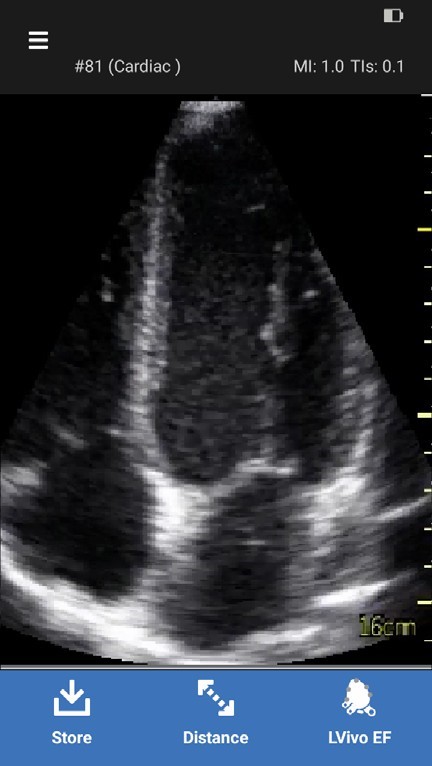

1. Scan the heart in apical 4 chamber view using the Cardiac preset.

NOTE: The LVivo EF app can only be used with the sector probe using the Cardiac preset.2. Adjust the image to see an optimized left ventricle.

3. Freeze the 4 chamber view immediately after visualizing the heart cycle to be measured.

LVivo EF app

4. Press LVivo EF icon to start the calculation.